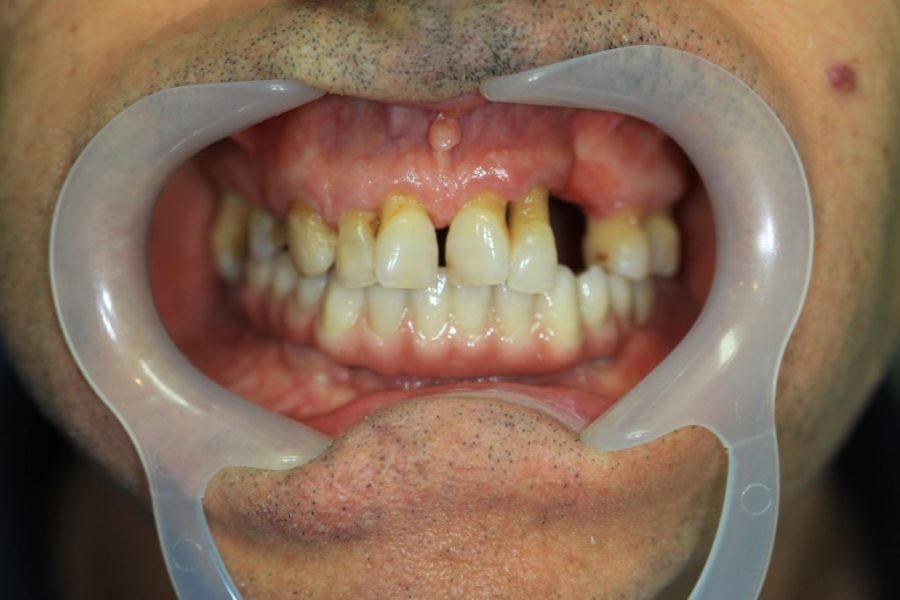

Mario’s Story: Fighting Gum Disease with Implants and Bridges

Mario came in with severe gum disease. We restored his lower teeth first, then placed four implants with a zirconium bridge for his upper teeth. Six months later, Mario’s new smile has become his favourite feature.